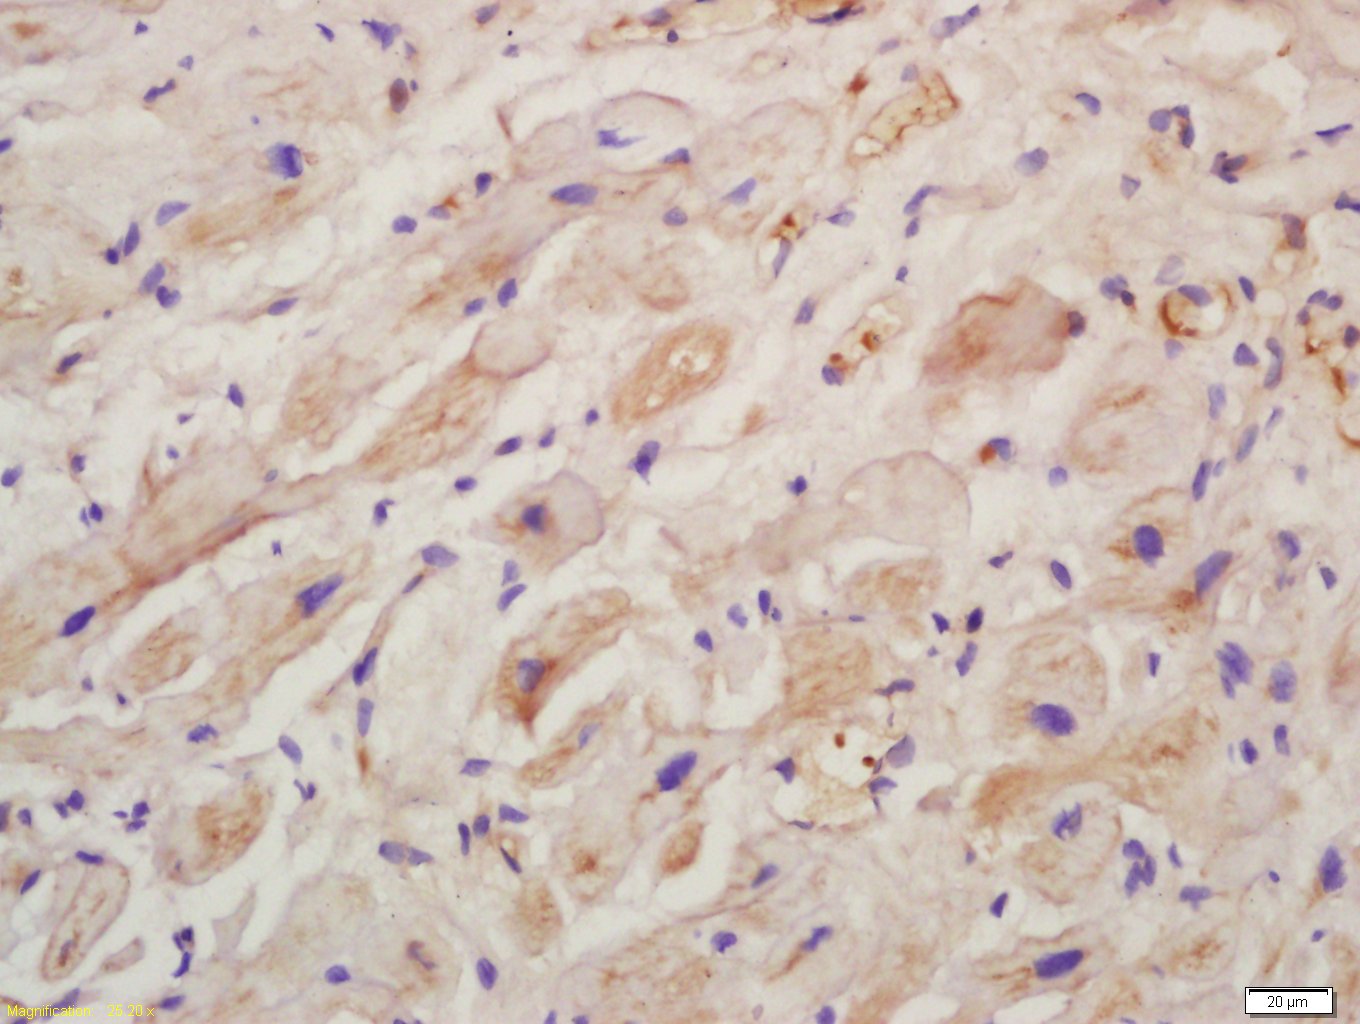

Paraformaldehyde-fixed, paraffin embedded (rat heart tissue); Antigen retrieval by boiling in sodium citrate buffer (pH6.0) for 15min; Block endogenous peroxidase by 3% hydrogen peroxide for 20 minutes; Blocking buffer (normal goat serum) at 37°C for 30min; Antibody incubation with (Collagen X) Polyclonal Antibody, Unconjugated (bs-0554R) at 1:400 overnight at 4°C, followed by a conjugated secondary (sp-0023) for 20 minutes and DAB staining.

Paraformaldehyde-fixed, paraffin embedded (Mouse brain); Antigen retrieval by boiling in sodium citrate buffer (pH6.0) for 15min; Block endogenous peroxidase by 3% hydrogen peroxide for 20 minutes; Blocking buffer (normal goat serum) at 37°C for 30min; Antibody incubation with (Collagen X) Polyclonal Antibody, Unconjugated (bs-0554R) at 1:400 overnight at 4°C, followed by operating according to SP Kit(Rabbit) (sp-0023) instructionsand DAB staining.

Paraformaldehyde-fixed, paraffin embedded (Rat brain); Antigen retrieval by boiling in sodium citrate buffer (pH6.0) for 15min; Block endogenous peroxidase by 3% hydrogen peroxide for 20 minutes; Blocking buffer (normal goat serum) at 37°C for 30min; Antibody incubation with (Collagen X) Polyclonal Antibody, Unconjugated (bs-0554R) at 1:400 overnight at 4°C, followed by operating according to SP Kit(Rabbit) (sp-0023) instructionsand DAB staining.